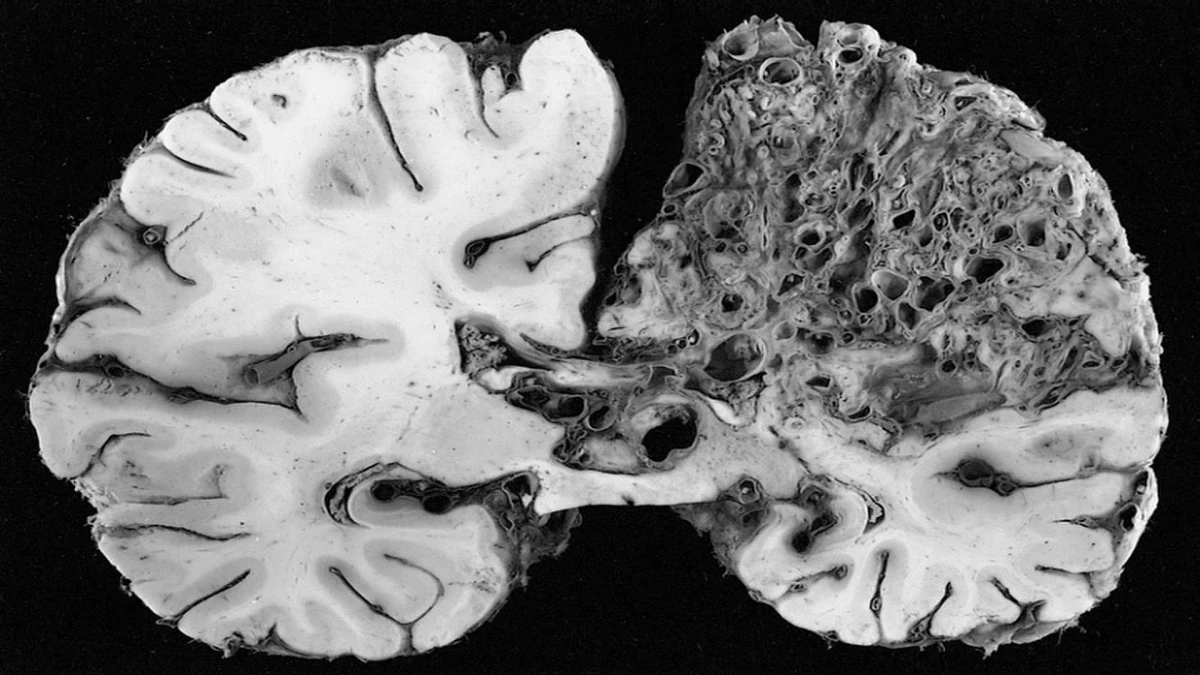

Прион грибы

Прион грибы 114 фото